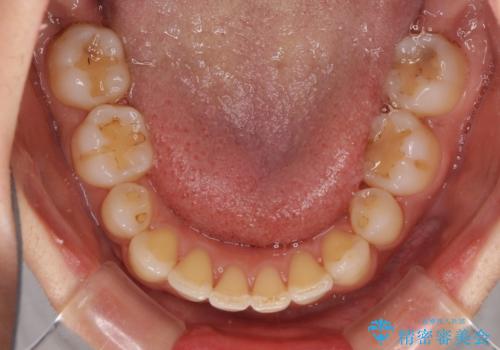

- 以前矯正治療をされていましたが、後戻りが起きたことを気にして来院された患者様です。

全顎的に認められた叢生を改善するため、インビザラインにて治療を行うこととしました。

前歯の叢生の改善を目的として、IPR(歯と歯の間を削る)と歯列全体の後方移動によって歯並びを整えることとしました。

毎日22時間の装着時間を守ってくださいましたが、ハイペースにマウスピースを交換することなく、慎重に治療を進めてくださったので、治療期間はやや長くなりました。

臼歯部も含め、叢生が綺麗に改善され、患者様には大変満足していただきました。